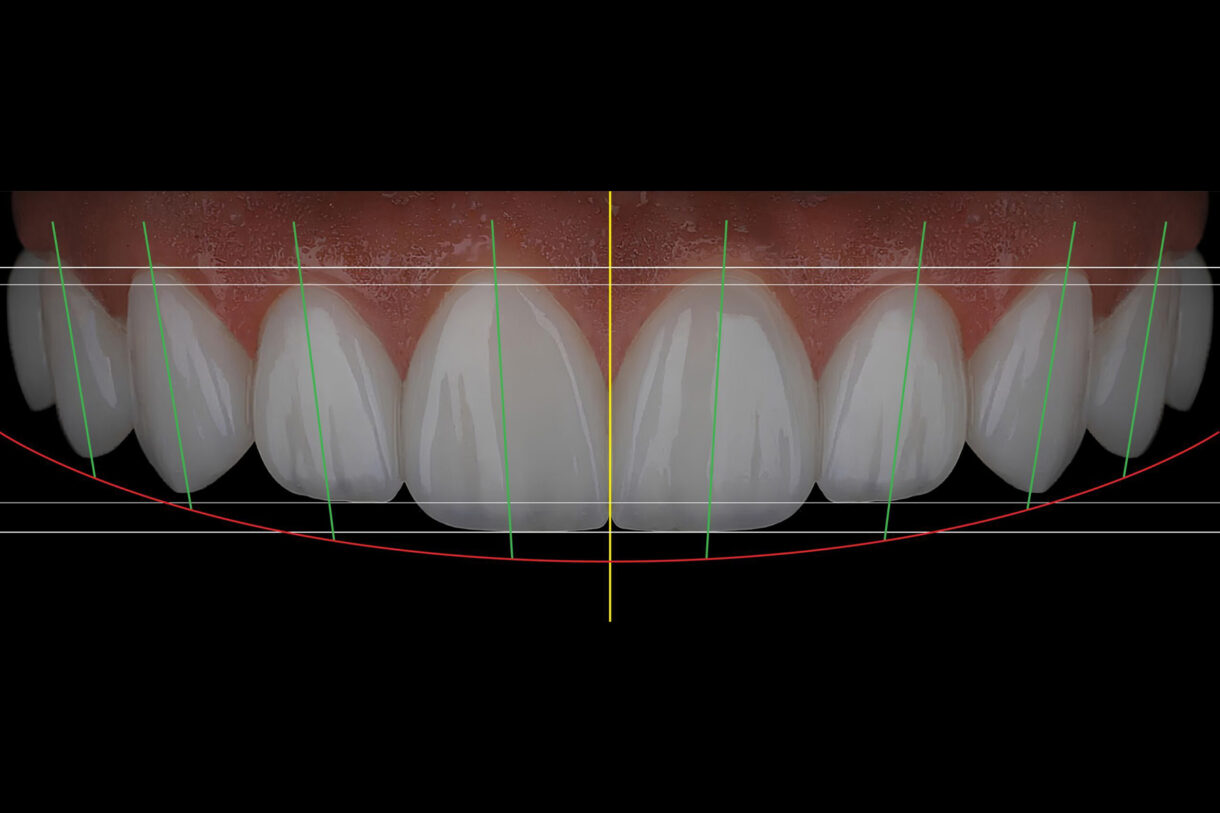

What is DIGITAL SMILE DESIGN? DIGITAL SMILE DESIGN is a work concept developed by Dr. Christian Coachman, and perfected by the development of modern technology. The unique advantage of digital planning is that it changes one of the basic obstacles in dentistry, which is that the patient sees his new teeth and smile only at the end of the procedure. Before...